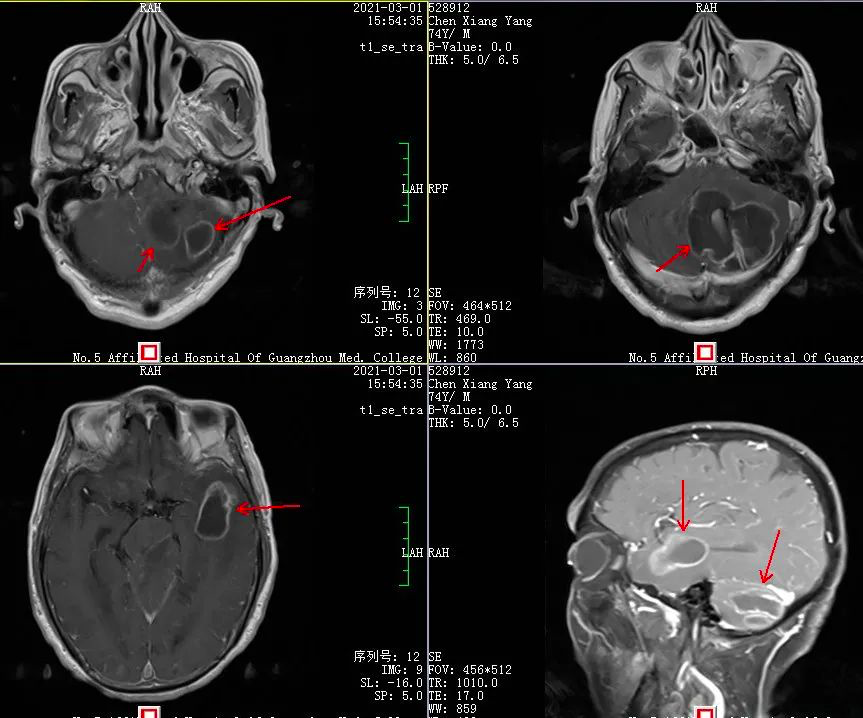

▲ 术前脓肿强化图像

几天后,由杨孔宾教授主刀,术中穿刺证实了杨教授的判断——陈伯确实为脑脓肿。此次手术首先切除较大的小脑的病变,抽吸出黄白色的粘稠脓液。手术在显微镜下微创切除了病变,完整切除了脓肿。

在神经外科组织科内讨论时,杨教授提出了一个新观点,他认为陈伯的这个病变呈环形强化,符合了“脑脓肿”的特点,很可能是陈伯患的是脑脓肿。

脑脓肿是颅内感染性病变,指化脓性细菌感染引起的化脓性脑炎、慢性肉芽肿及脑脓肿包膜形成,少部分也可是真菌及原虫侵入脑组织而致脑脓肿。临床表现和胶质瘤、脑转移瘤相似,典型症状头疼、局限性神经功能缺陷和进行性的行为及认知功能障碍,仅半数患者有发热症状。

尽管陈伯未有过发热史或脓肿的相关疾病等脑脓肿的常见特征,然而老年人还存在因免疫力低下而导致脑脓肿这一可能性。